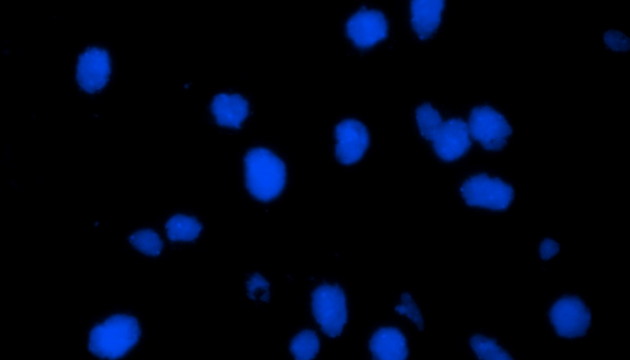

荧光原位杂交(Fluorescence In Situ Hybridization,FISH)是临床病理检测中广泛运用的一种分子细胞遗传学诊断技术,其原理是用荧光染料直接或间接标记的DNA核酸探针与待测样本中的DNA核酸序列按照碱基互补配对的原则进行杂交,然后通过荧光显微镜观察荧光信号位置、数量等来判断待测序列的缺失、扩增及易位等情况。其高分辨率、直接反映异常细胞比例、快速简便的特点,使其成为临床检测、预后评估及用药指导的重要工具。

FISH技术面临荧光弱、背景噪声、多通道叠加等难点。为了保障荧光信号强度,一般需要用到研究级荧光显微镜,半复消色差或以上的物镜,以及高功率的LED荧光光源或汞灯光源;为了去除背景噪声,一般需要搭配高截止深度的滤光片和高灵敏度相机;多通道叠加时要提取红绿信号点,然后放到蓝色DAPI信号上,处理需要相当的技巧。